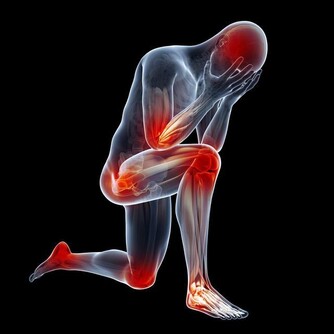

另外,值得一提的是,我在查房的時候,經常遇到患者詢問,大夫,我后腰疼,是不是腎壞了。

其實,正如我之前說的,腎臟是個非常沉默的器官,它的表面是沒有痛覺神經的,

大部分的腰痛現象與腎臟並無關係,但也不能排除腎結石活動期時,腎區可能會產生劇烈疼痛。